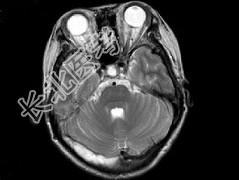

- 单项选择题女,37岁, 产后10天,出现剧烈头痛头昏伴神志不清2天, 根据所提供图像,最可能的诊断是 ( )

A、右侧蛛网膜下腔出血

B、右侧脑膜脑炎

C、右侧硬膜下血肿

D、右侧脑梗死

E、右侧静脉窦血栓形成